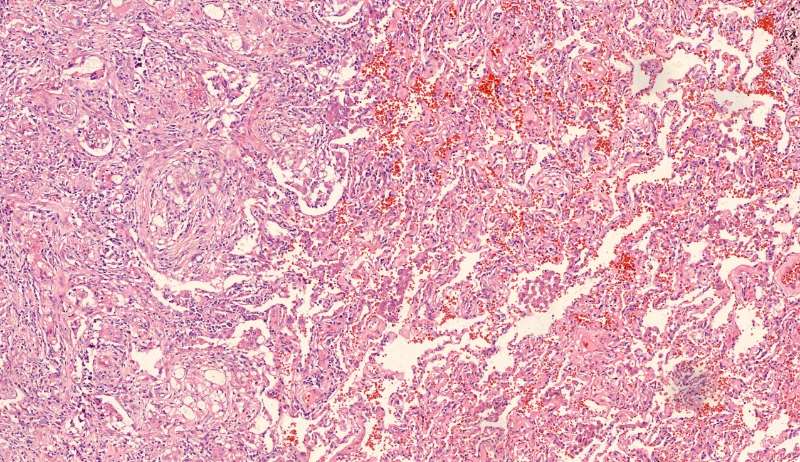

第二例隐球菌

整体是个类圆形,边界模糊(有晕征的感觉),肉芽肿一般都这样 里面也能见到许多小白球,大小从3微米到20微米不等 红细胞直径5-6微米 普通小淋巴细胞直径5微米 这里淋巴细胞挺多 有许多淋巴细胞,成堆

多核巨噬细胞吞了许多隐球菌 经常是反包围的感觉

这三幅是周围区,也有巨噬细胞,单核的多 都在肺泡腔内 所以有ggo样密度 过一段时间,晕就消失,有时是消退,有时是实性区扩大,盖住磨玻璃晕 那也是吞噬的作用,常代表免疫力正常 就是警察多了把肺泡填了